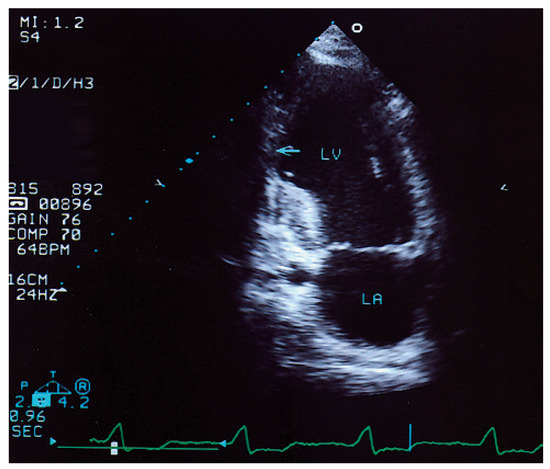

Summary. We report two cases of a 83- and a 78-year-old female with tetralogy of Fallot (TOF) who underwent operation at an advanced age in their 30’s, making them the oldest patients repaired for tetralogy of Fallot [...]